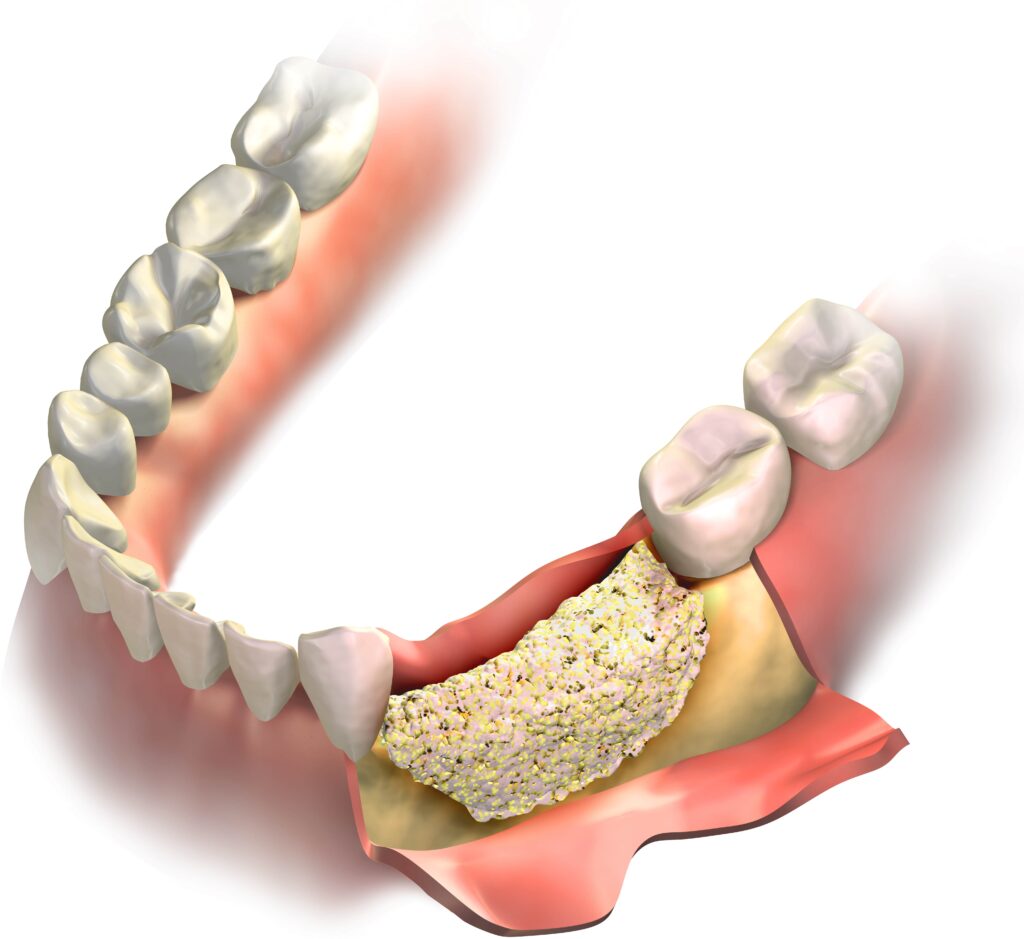

Adequate Bone Structure

For an implant to be successfully placed and sustained, there must be sufficient bone density and volume in the jaw to support it. Bone loss, which often occurs following tooth loss, can compromise the stability of an implant. However, procedures like bone grafting can be performed to enhance the jawbone’s suitability for implants, although this can lengthen the overall treatment time and cost.